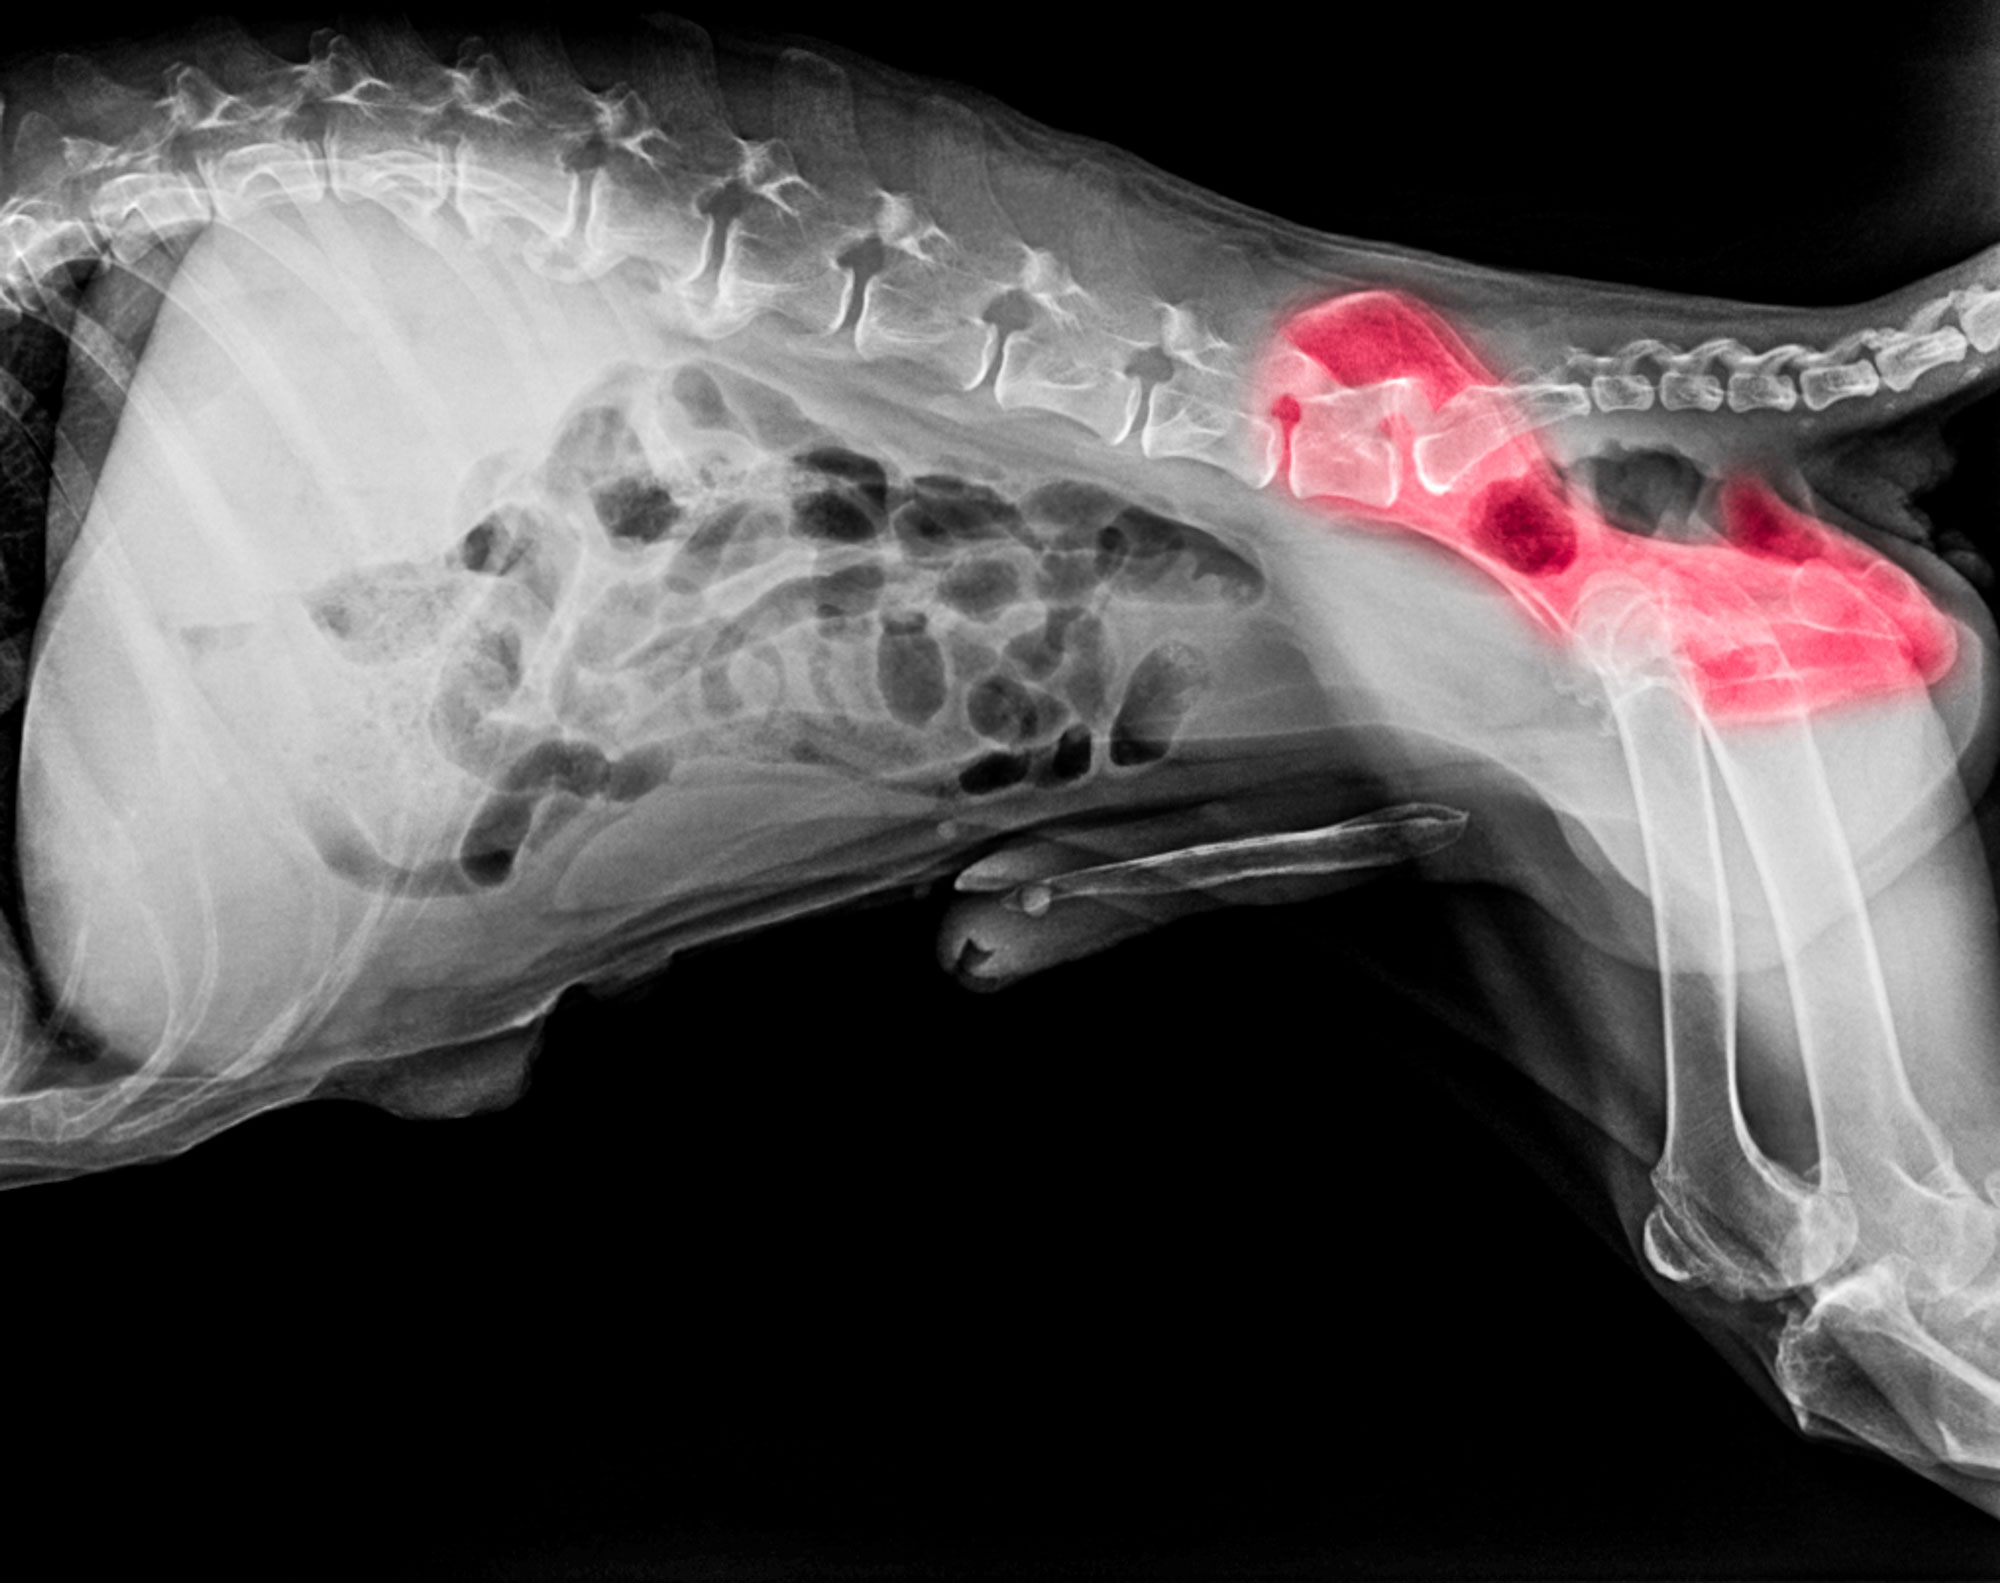

An ultrasound image showing a dog’s heart; each of the chambers are labelled. Blood flow from the left atrium (LA) is upwards through the mitral valve (MV) and into the left ventricle (LV). The mitral valve acts as a one-way valve.

The same image as above, with the computer colour coding showing the direction of blood flow. When the left ventricle (LV) pumps, the mitral valve should prevent any backflow. In this instance there is a jet of blood regurgitating back into the left atrium (LA).